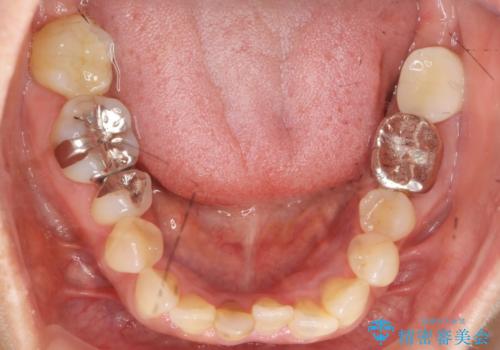

移植後、生着を待って根管治療及び補綴修復を行いました。

親知らずの移植により、自分の歯を用いて咬合機能を回復することができ、大変喜んで頂けました。

被せ物の種類:オールセラミッククラウン スタンダード